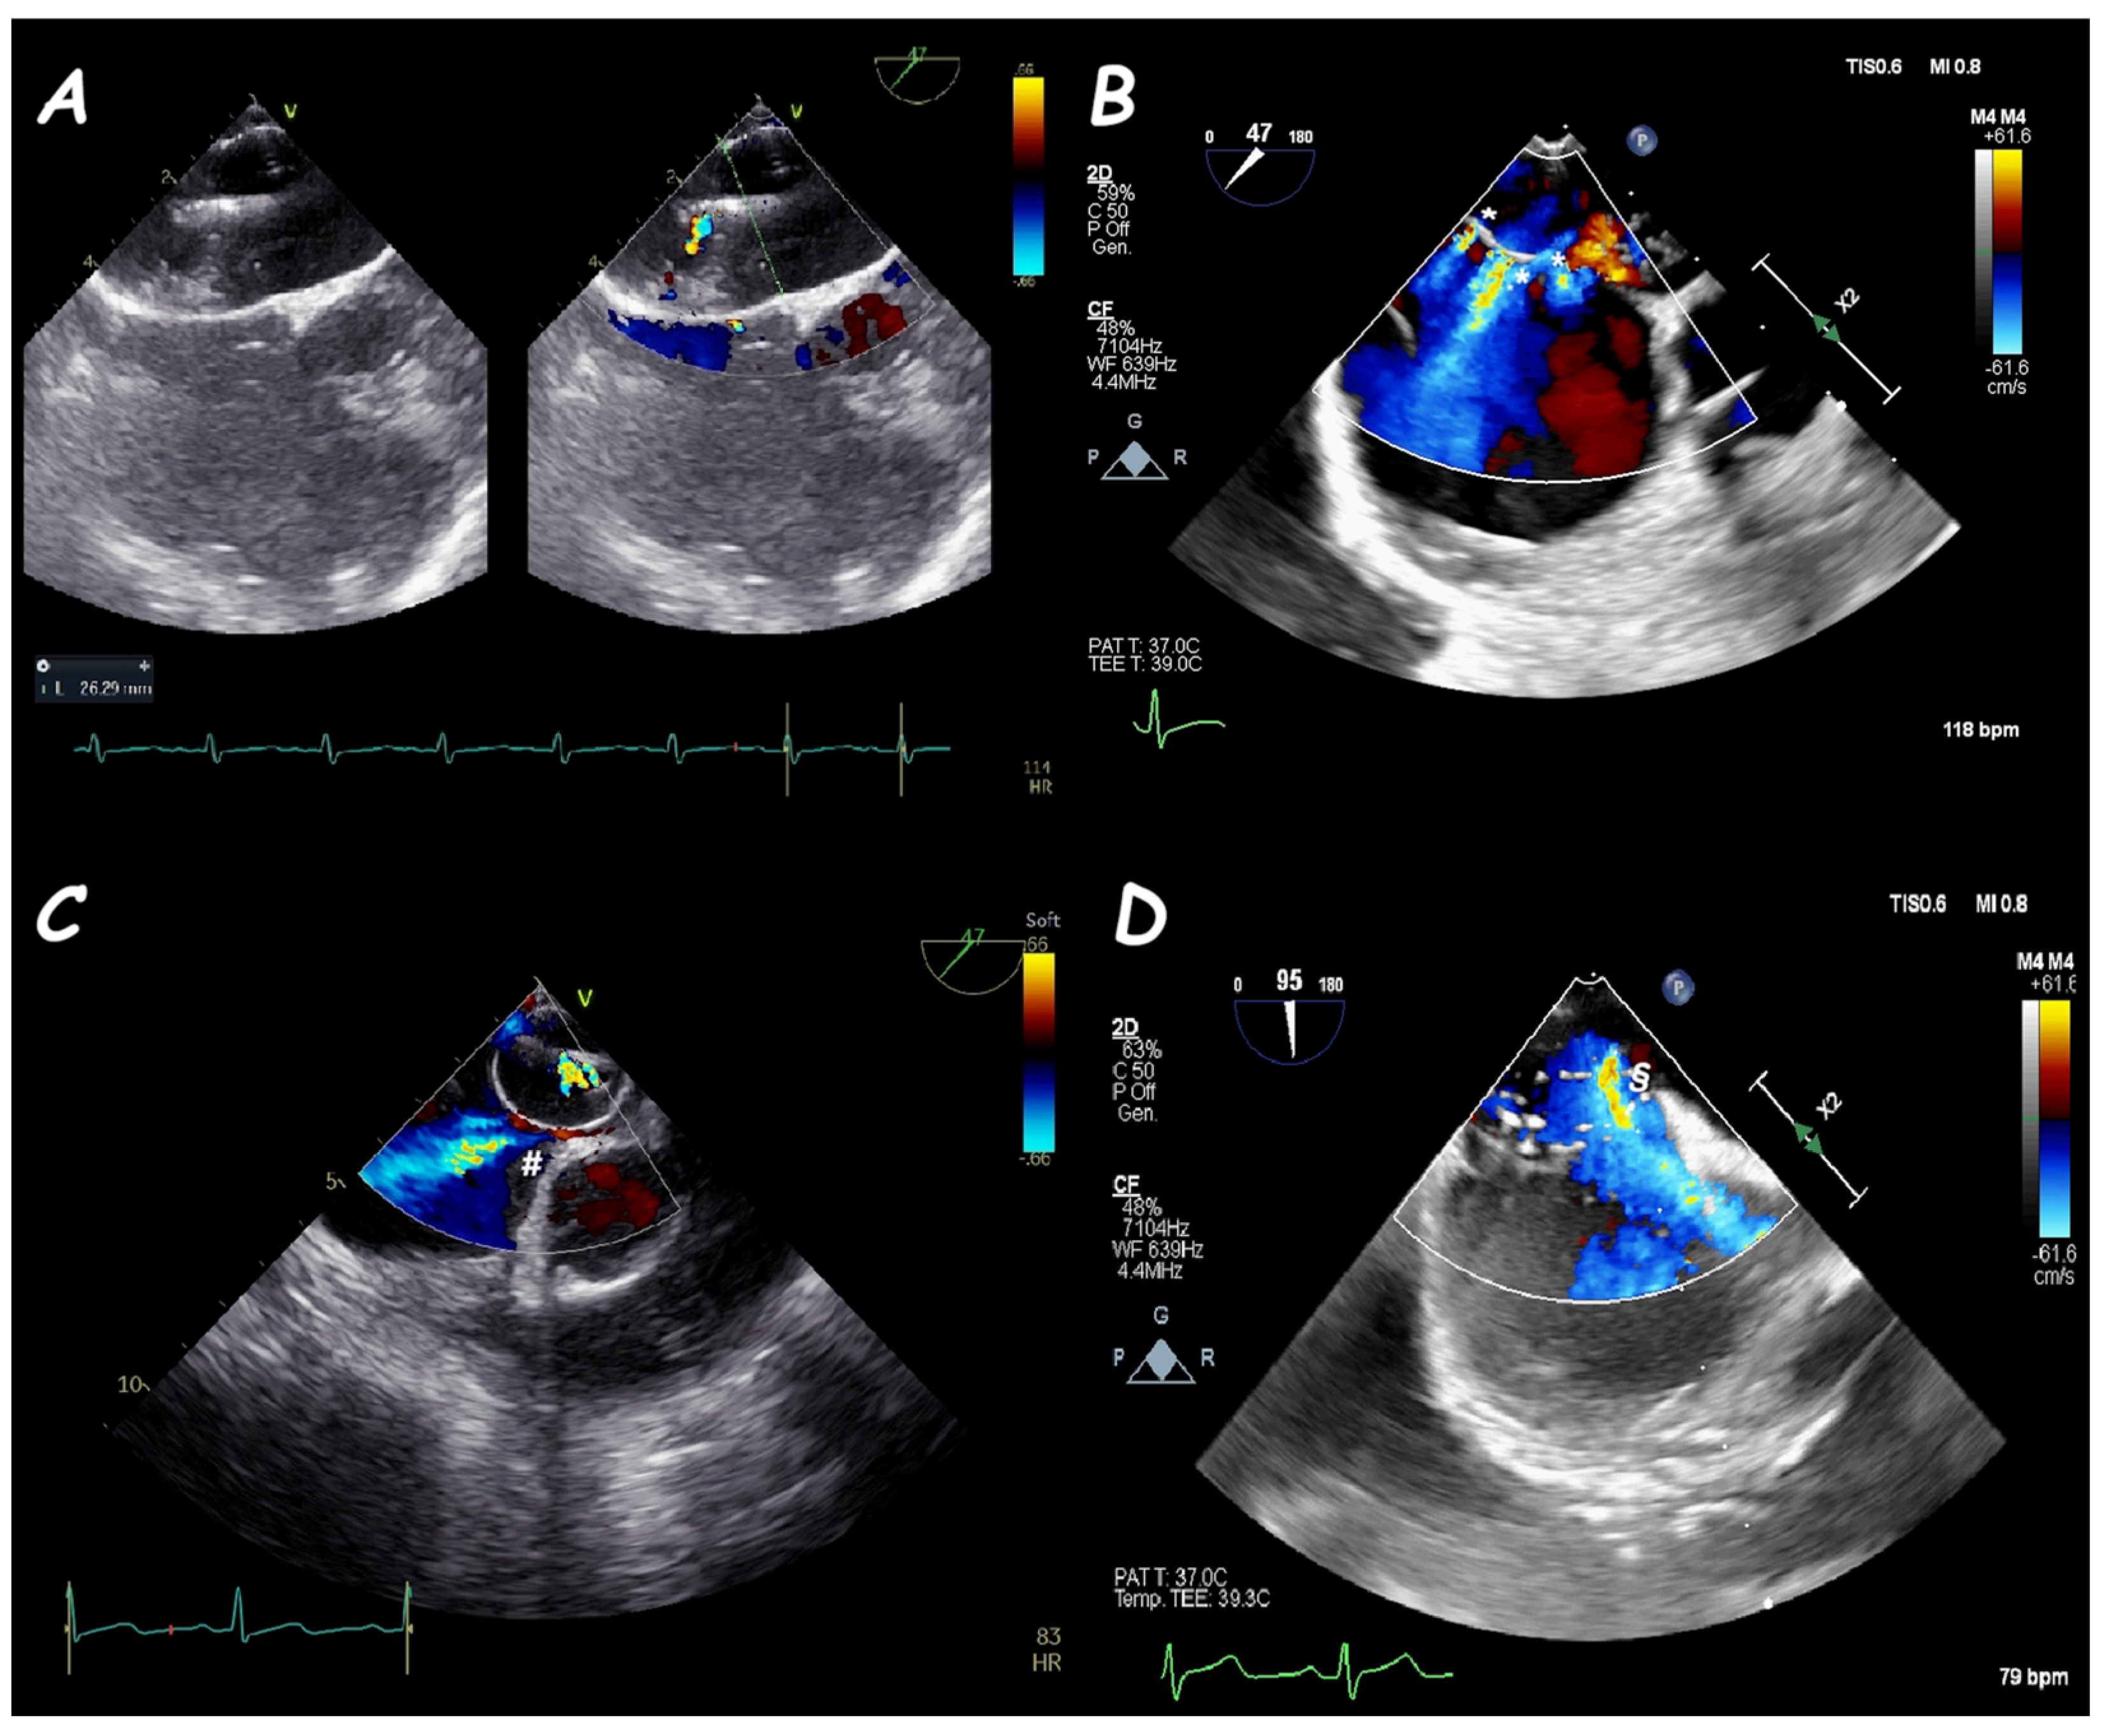

5. Fontan Conduit Fenestration Management

6. Ruptured Sinus of Valsalva Closure